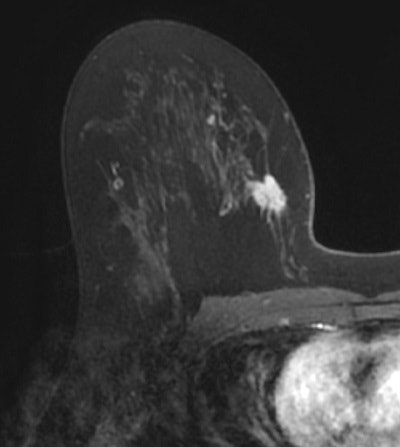

In a new phase I clinical trial, clinicians at Brigham and Women's Hospital (BWH) in Boston found significant differences and additional information on breast deformity and tumor position in intraoperative supine MR images, which ideally would lead to more effective cancer removal, compared to images from a more conventional preoperative prone MRI scan.

The dilemma is that preoperative MR images are taken from a prone position, but the patient is in the supine position (face up, on her back) for surgery with gravity naturally changing the shape of the breast.

In reviewing images from the preoperative prone MR with images from the intraoperative supine MR, the researchers found tumor displacement in the six patients who had both prone and supine MRI scans. The average tumor displacement was 23.8 mm in the lateral coordinate, -27.7 mm in the anterior coordinate, and -6.5 mm in the superior coordinate. As expected, tumors were closer to the chest wall on supine images than on prone images.

There were also noticeable changes in tumor formation, such as volume, surface area, and sphericity, with the different patient positions.